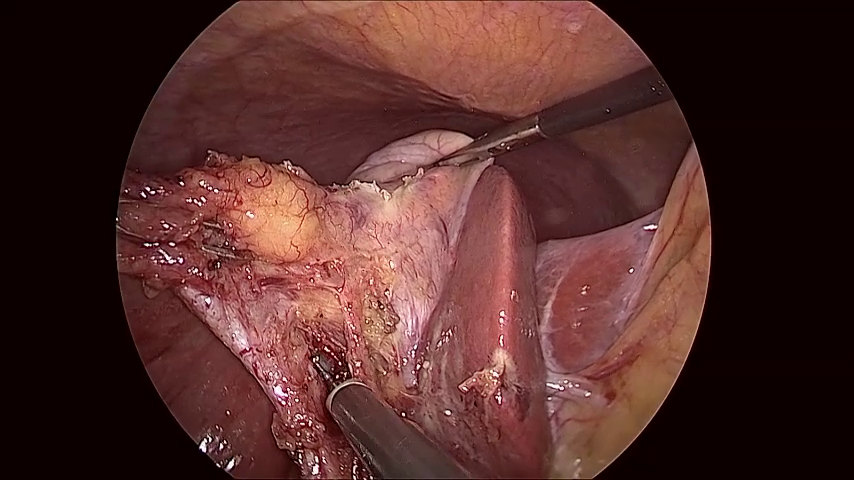

Refer to caption

(a) The dark right-hand side of the content area is missed by both variants. The learned variant gets a slightly better fit, this could be due to a better positioing of points on the left-hand side of the content area.

(b) A noisy and bright border poses a challenge for the handcrafted variant. Too few edge points are detected to make a confident estimate of the circle. The learned variant manages to correctly identify the right-hand edge of the content area, however, the circle fits to incorrect edge points found on the blacked out secondary video feed in the top-left.

(c) Both variants correctly identify the edge in the bottom-left but mistake dark regions in the top-right and bottom-right corners as border regions. The learned variant rejects the final circle as the circle score is too low. This scenario, where a single corner of the image is outside the content area, features prominantly in our failure cases.

(d) In this sample, the handcrafted variant detects edge points in the bottom-left, but scores them poorly. The circle fitting then chooses the incorrectly identified edge points in the top-left. The learned variant scores the detected points in the bottom-left higher, and so the circle fitting finds a satisfying result.

Figure 6: A selection of failure cases of our algorithm taken from the RobustECA dataset, the results of both the handcrafted (left) and learned (right) variants are shown for each image. The edge of the ground truth and inferred circular image projections are shown in blue, and green, respectively. Points indicate the position of detected edge points, the colour of each point indicates its score, going from red to green as the score increases. The vector found when calculating the Hausdorff distance is shown in yellow.